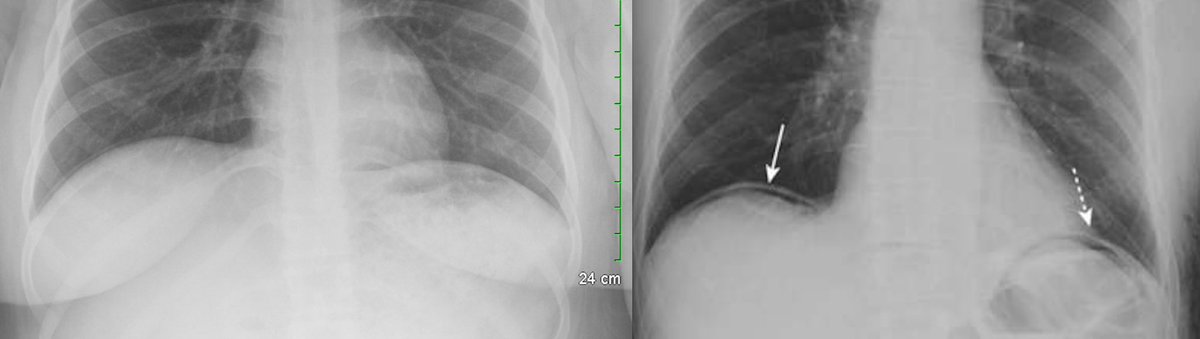

⚪️Air Under the diaphragm (somtimes the crescent 🌙 Sign) ➡️ indicates pneumoperitonium

✳️Think of perforated Viscus